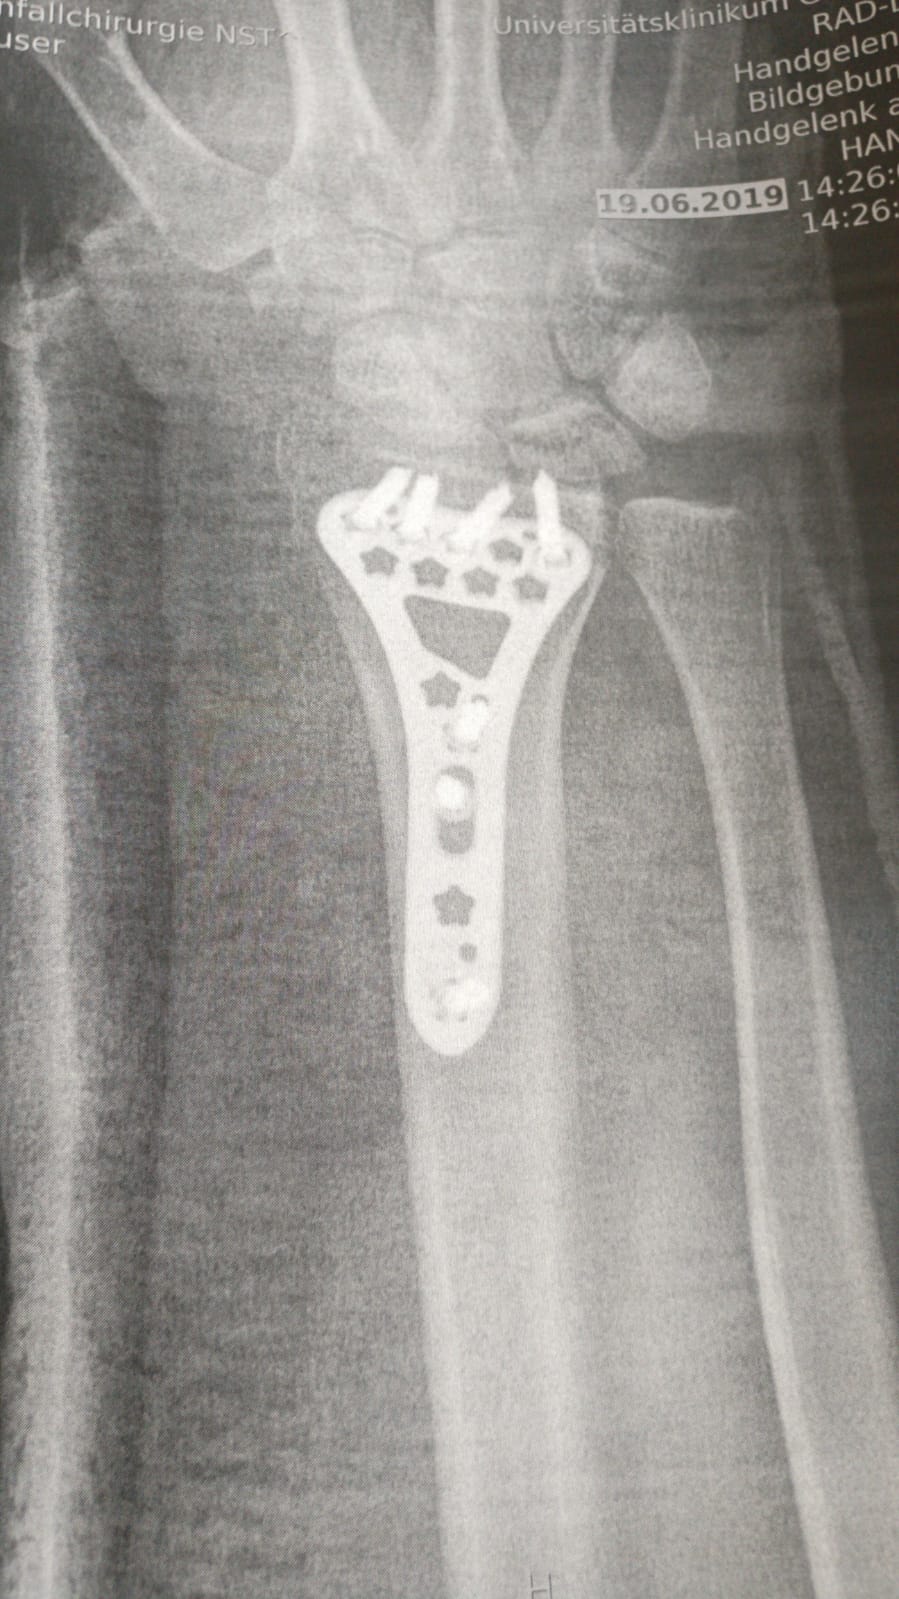

Got to leave the Hospital today. Surgery was on tuesday instead of monday

On the positive you got some nice new titanium hardware! Quick heals and good feels being sent your way brother.